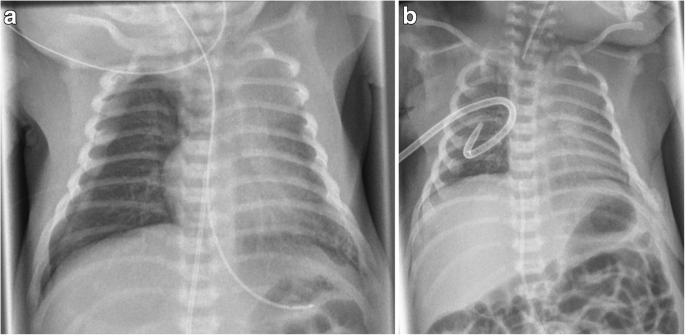

After good postnatal adaptation, the infant needed mechanical ventilation due to respiratory distress caused by a spontaneous right-sided pneumothorax at the age of 1 h. He quickly stabilized after nasotracheal intubation and placement of a chest tube. Neither signs of pulmonary hypoplasia nor pulmonary hypertension were evident from chest x-ray or echocardiography (see Fig. 1a and b). Pre- and postductal oxygen saturation monitoring did not show any significant difference, ventilatory support was minimal (SIMV-mode, PIP 13 mbar, FiO2 0,25) and the patient had no signs of surfactant deficiency.